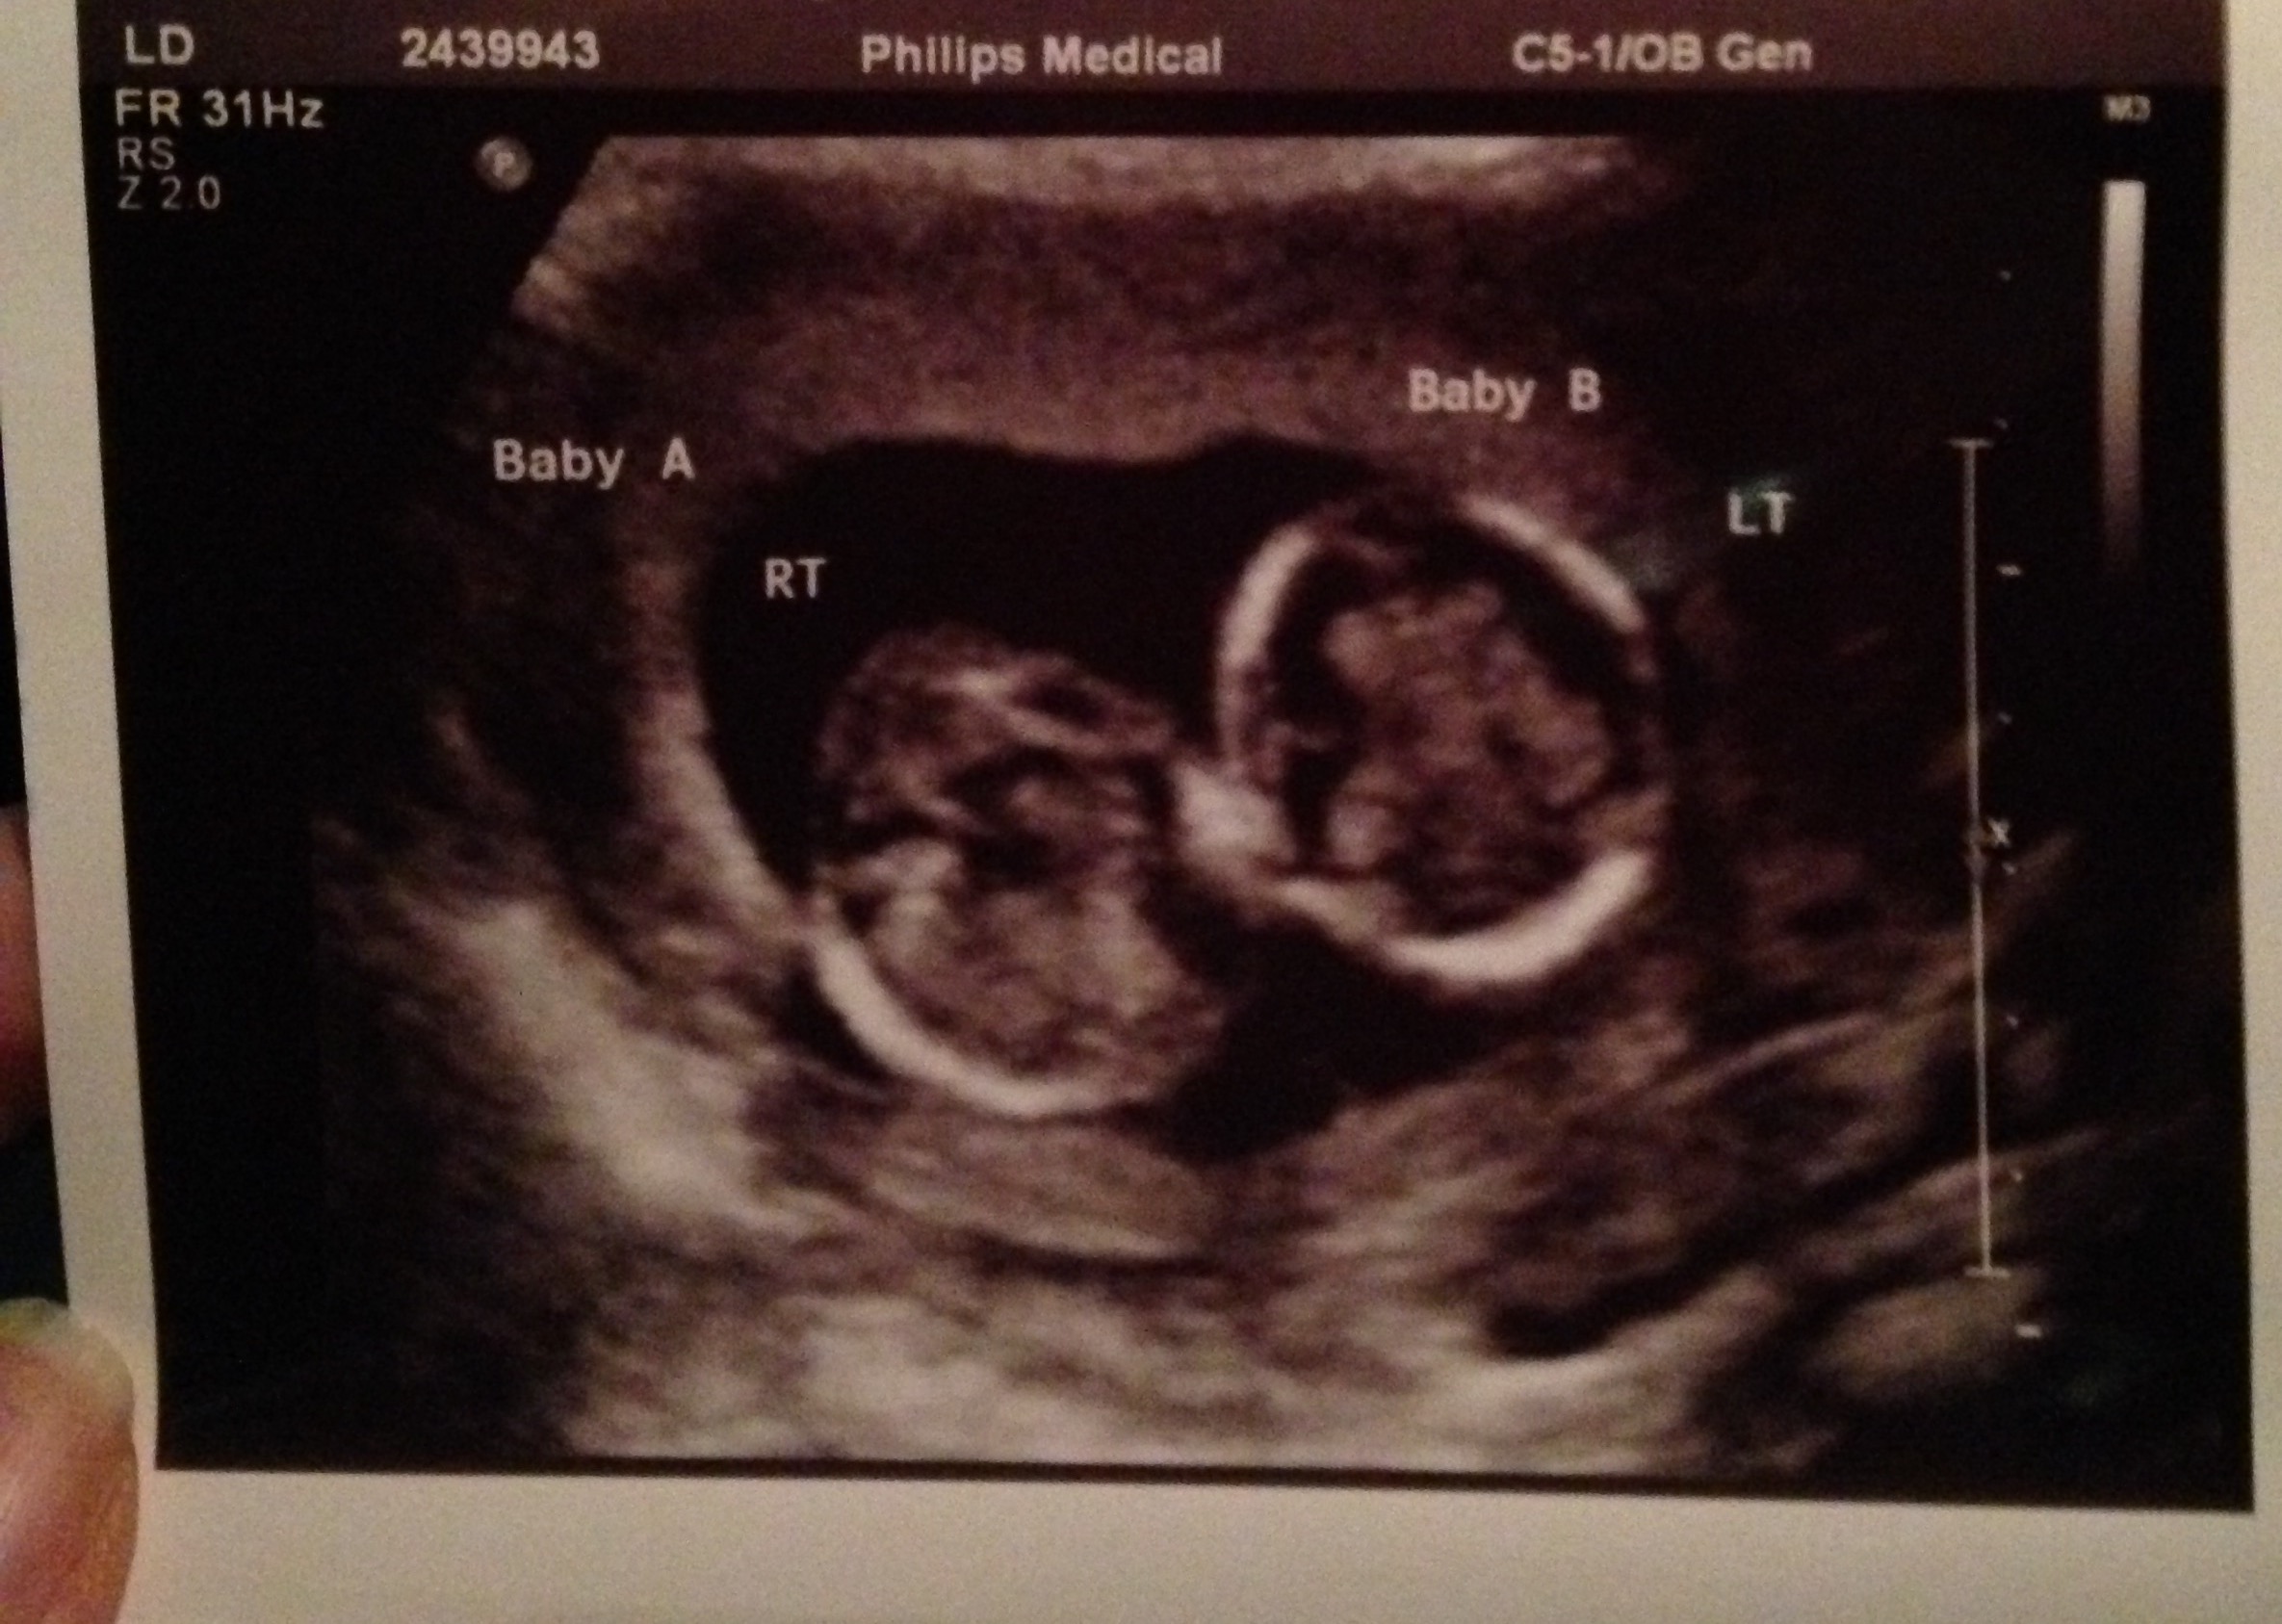

Had unscheduled ultrasound due to unexplained bleeding. Still don't know why I'm spotting (grr) but both babies were okay. 14+4 at the time of the scan. Baby A refused to face the camera.